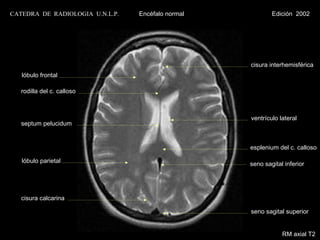

CATEDRA DE RADIOLOGIA U.N.L.P.   Encéfalo normal           Edición 2002

cisura interhemisférica

lóbulo frontal

rodilla del c. calloso

ventrículo lateral

septum pelucidum

esplenium del c. calloso

lóbulo parietal                                 seno sagital inferior

cisura calcarina

seno sagital superior

RM axial T2